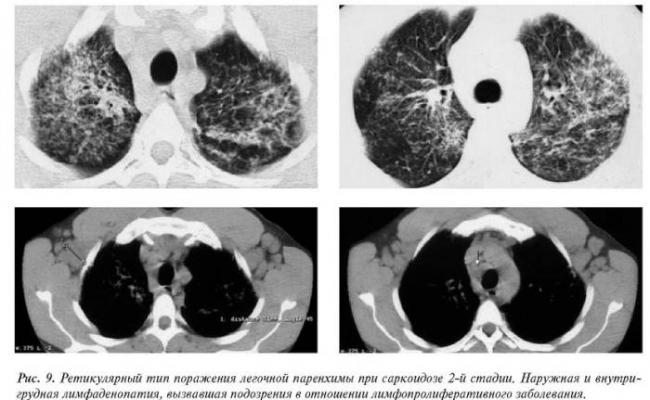

- Перилимфатический очаг – часто наблюдается в бронхах, сосудах, в междольковых перегородках и листках плевры. В таком случае видны неровные контуры анатомических структур, при этом перегородочки и стенки бронхов несколько утолщены, как и стенки сосудов. Подобные патологические изменения часто встречаются при туберкулёзе, силикозе, саркоидозе и карциноматозе. При этих патологиях очаги небольшие и не превышают 2-5 мм. Состоят такие очаги из гранулем или метастатических узелочков, они наблюдаются вдоль лимфатических узелков в ткани лёгких и плевре.

- Полиморфный очаг. Такие очаговые образования в ткани лёгких возникают при туберкулёзе. В этом случае КТ позволяет увидеть участки разной плотности и размеров. В некоторых случаях такая картина наблюдается при онкологических патологиях.